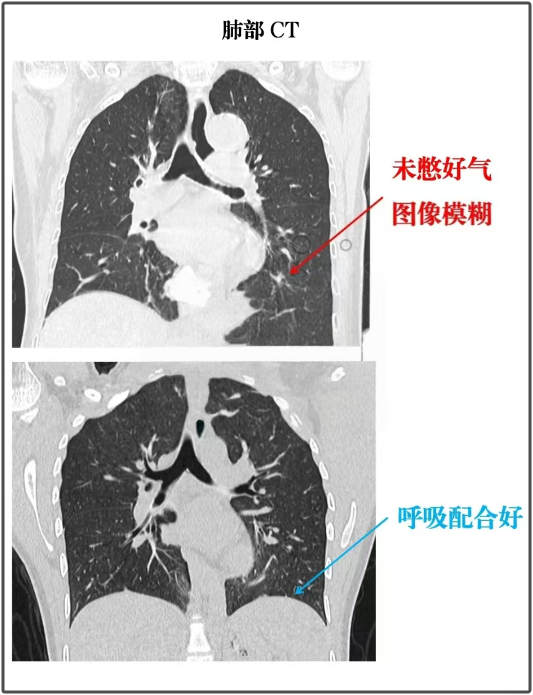

发现肺结节,复查时不要犯这4个错误!